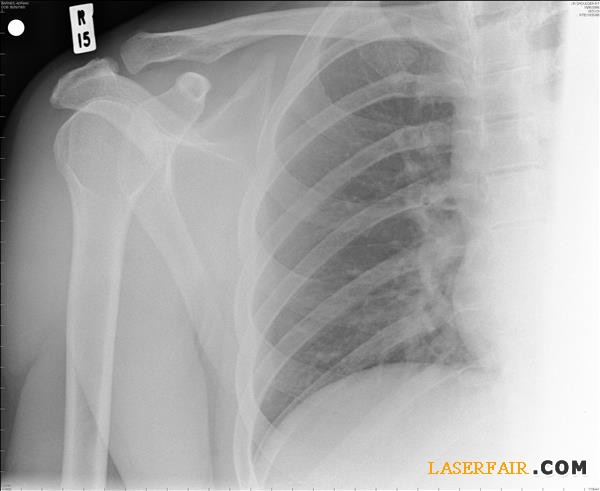

如今,很多非常先進和創(chuàng)新的醫(yī)療手術(shù)要依賴于3D打印來填補受損的骨骼。“我們準備了一種基于羥基磷灰石的液狀材料,可以通過3D打印機進行打印。”研究團隊的Vitaly Guzeev教授解釋說。他給出了一個顱腦損傷男性患者的例子。其受傷部位經(jīng)過3D掃描,然后將數(shù)據(jù)發(fā)送到3D打印機處,由其復(fù)制出受損失去的部分骨骼。這種“骨水泥”會在3D打印過程中變硬。